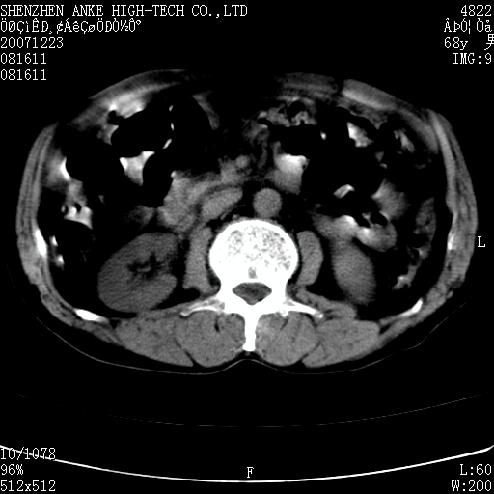

未见异常,病人差闭气,伪影较多.

肠管积气明显.

肠道准备不好,干扰影大。

肠道气体伪影干扰太大了,应该是干扰所致,未见明显异常。

上腹部ct平扫未见明显异常。(肠道气体较多,患者呼吸了)